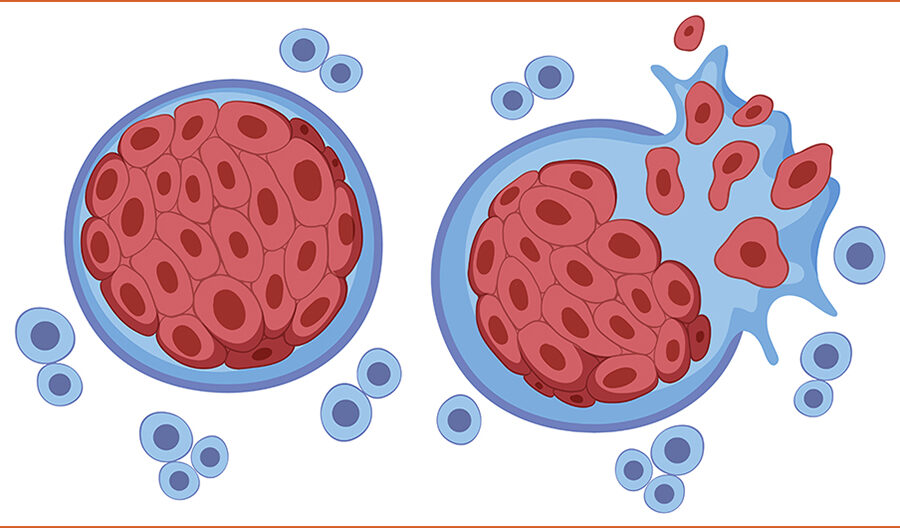

फ्रान्सेली वैज्ञानिकहरूले अहिले एमआरएनए खोपलाई अल्ट्रासाउन्ड प्रविधिसँग संयोजन गर्दै नवीन उपचारप्रति आशा जगाइरहेका छन् । “अत्यन्त आक्रामक क्यान्सरसँग जुध्न प्रतिरक्षा कोषहरूलाई सिकाउन एमआरएनए प्रयोग गर्ने हाम्रो धारणा हो”, बेयेले स्पष्ट पारे।

यस विधिमा पहिलो चरणका रूपमा शक्तिशाली अल्ट्रासाउन्ड मार्फत तन्तुभित्र कम्पन पैदा गरिन्छ, जसले ग्यासका साना फोका बनाउँछ । “जब ती फोका फुट्छन्, तिनीहरूले अग्नाशय वरिपरि रहेको कडा अवरोध-एक प्रकारको ‘बङ्कर’-लाई भत्काइदिन्छन्, जसले एमआरएनए खोपलाई ट्युमरसम्म सहजै प्रवेश गर्न मद्दत गर्छ”, बेये भन्छन्।